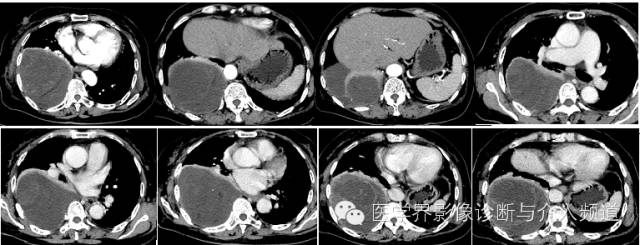

【影像图像】

【影像学表现】

右侧胸腔内见巨大囊性占位,内夹杂少许小片状脂肪及点状钙化灶。内可见分隔。增强动脉期内见血管影走形,静脉期可见病变轻度强化,CT值约为30 Hu,内分隔强化明显。

CT表现为肿块较大,瘤内含有脂肪性密度较具特征性,并可见点状钙化,中间见网状分隔,可形成假包膜。由于血供多不丰富,增强后仅见间隔轻微强化。